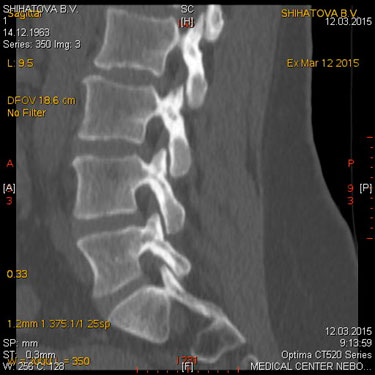

МСКТ позвоночника и спинного мозга.

Метод МСКТ очень ценен для выявления дегенеративно-дистрофических изменений, диагностируются грыжи дисков и элементы, суживающие позвоночный канал. МРТ превосходит визуализацию спинного мозга, содержимое дурального мешка, возможность увидеть другие уровни. Однако для пациентов с типичным течением болезни локализацией симптомов на одном уровне с одной стороны МСКТ обычно достаточна для постановки диагноза.

Показания:

- подозрение на опухолевое, метастатическое поражение с деструкцией

- травматическое поражение

- подозрение на грыжу диска (с обязательным указанием сегмента поражения) при невозможности проведения МРТ

- воспалительные процессы (специфические и неспецифические) с деструкцией костных структур

Подготовка: не требуется. Предварительное рекомендуемое обследование: заключение невролога